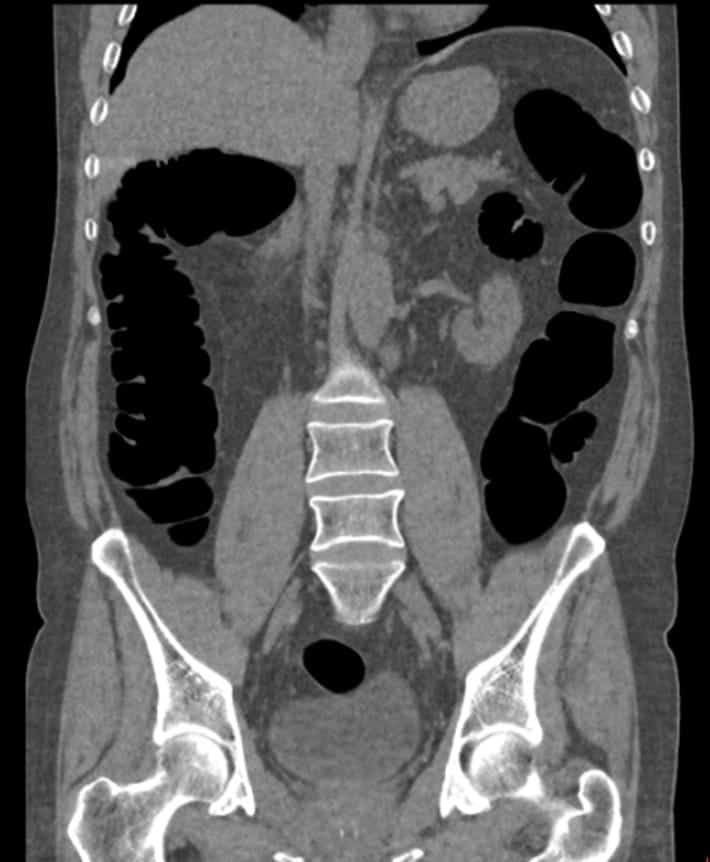

Virtual Colonoscopy Moderate Diverticulosis Ct Scan RoyaltyFree Stock Does Medicare Cover Ct Virtual Colonoscopy Use this page to view details for the local coverage determination for virtual colonoscopy (ct colonography). At this time, medicare does not cover the cost of virtual colonoscopy (ct colonography). Typically, a virtual colonoscopy is not covered by original medicare. But, if you have medicare benefits through part b, you may have. When this happens, your doctor may have you. Does Medicare Cover Ct Virtual Colonoscopy.